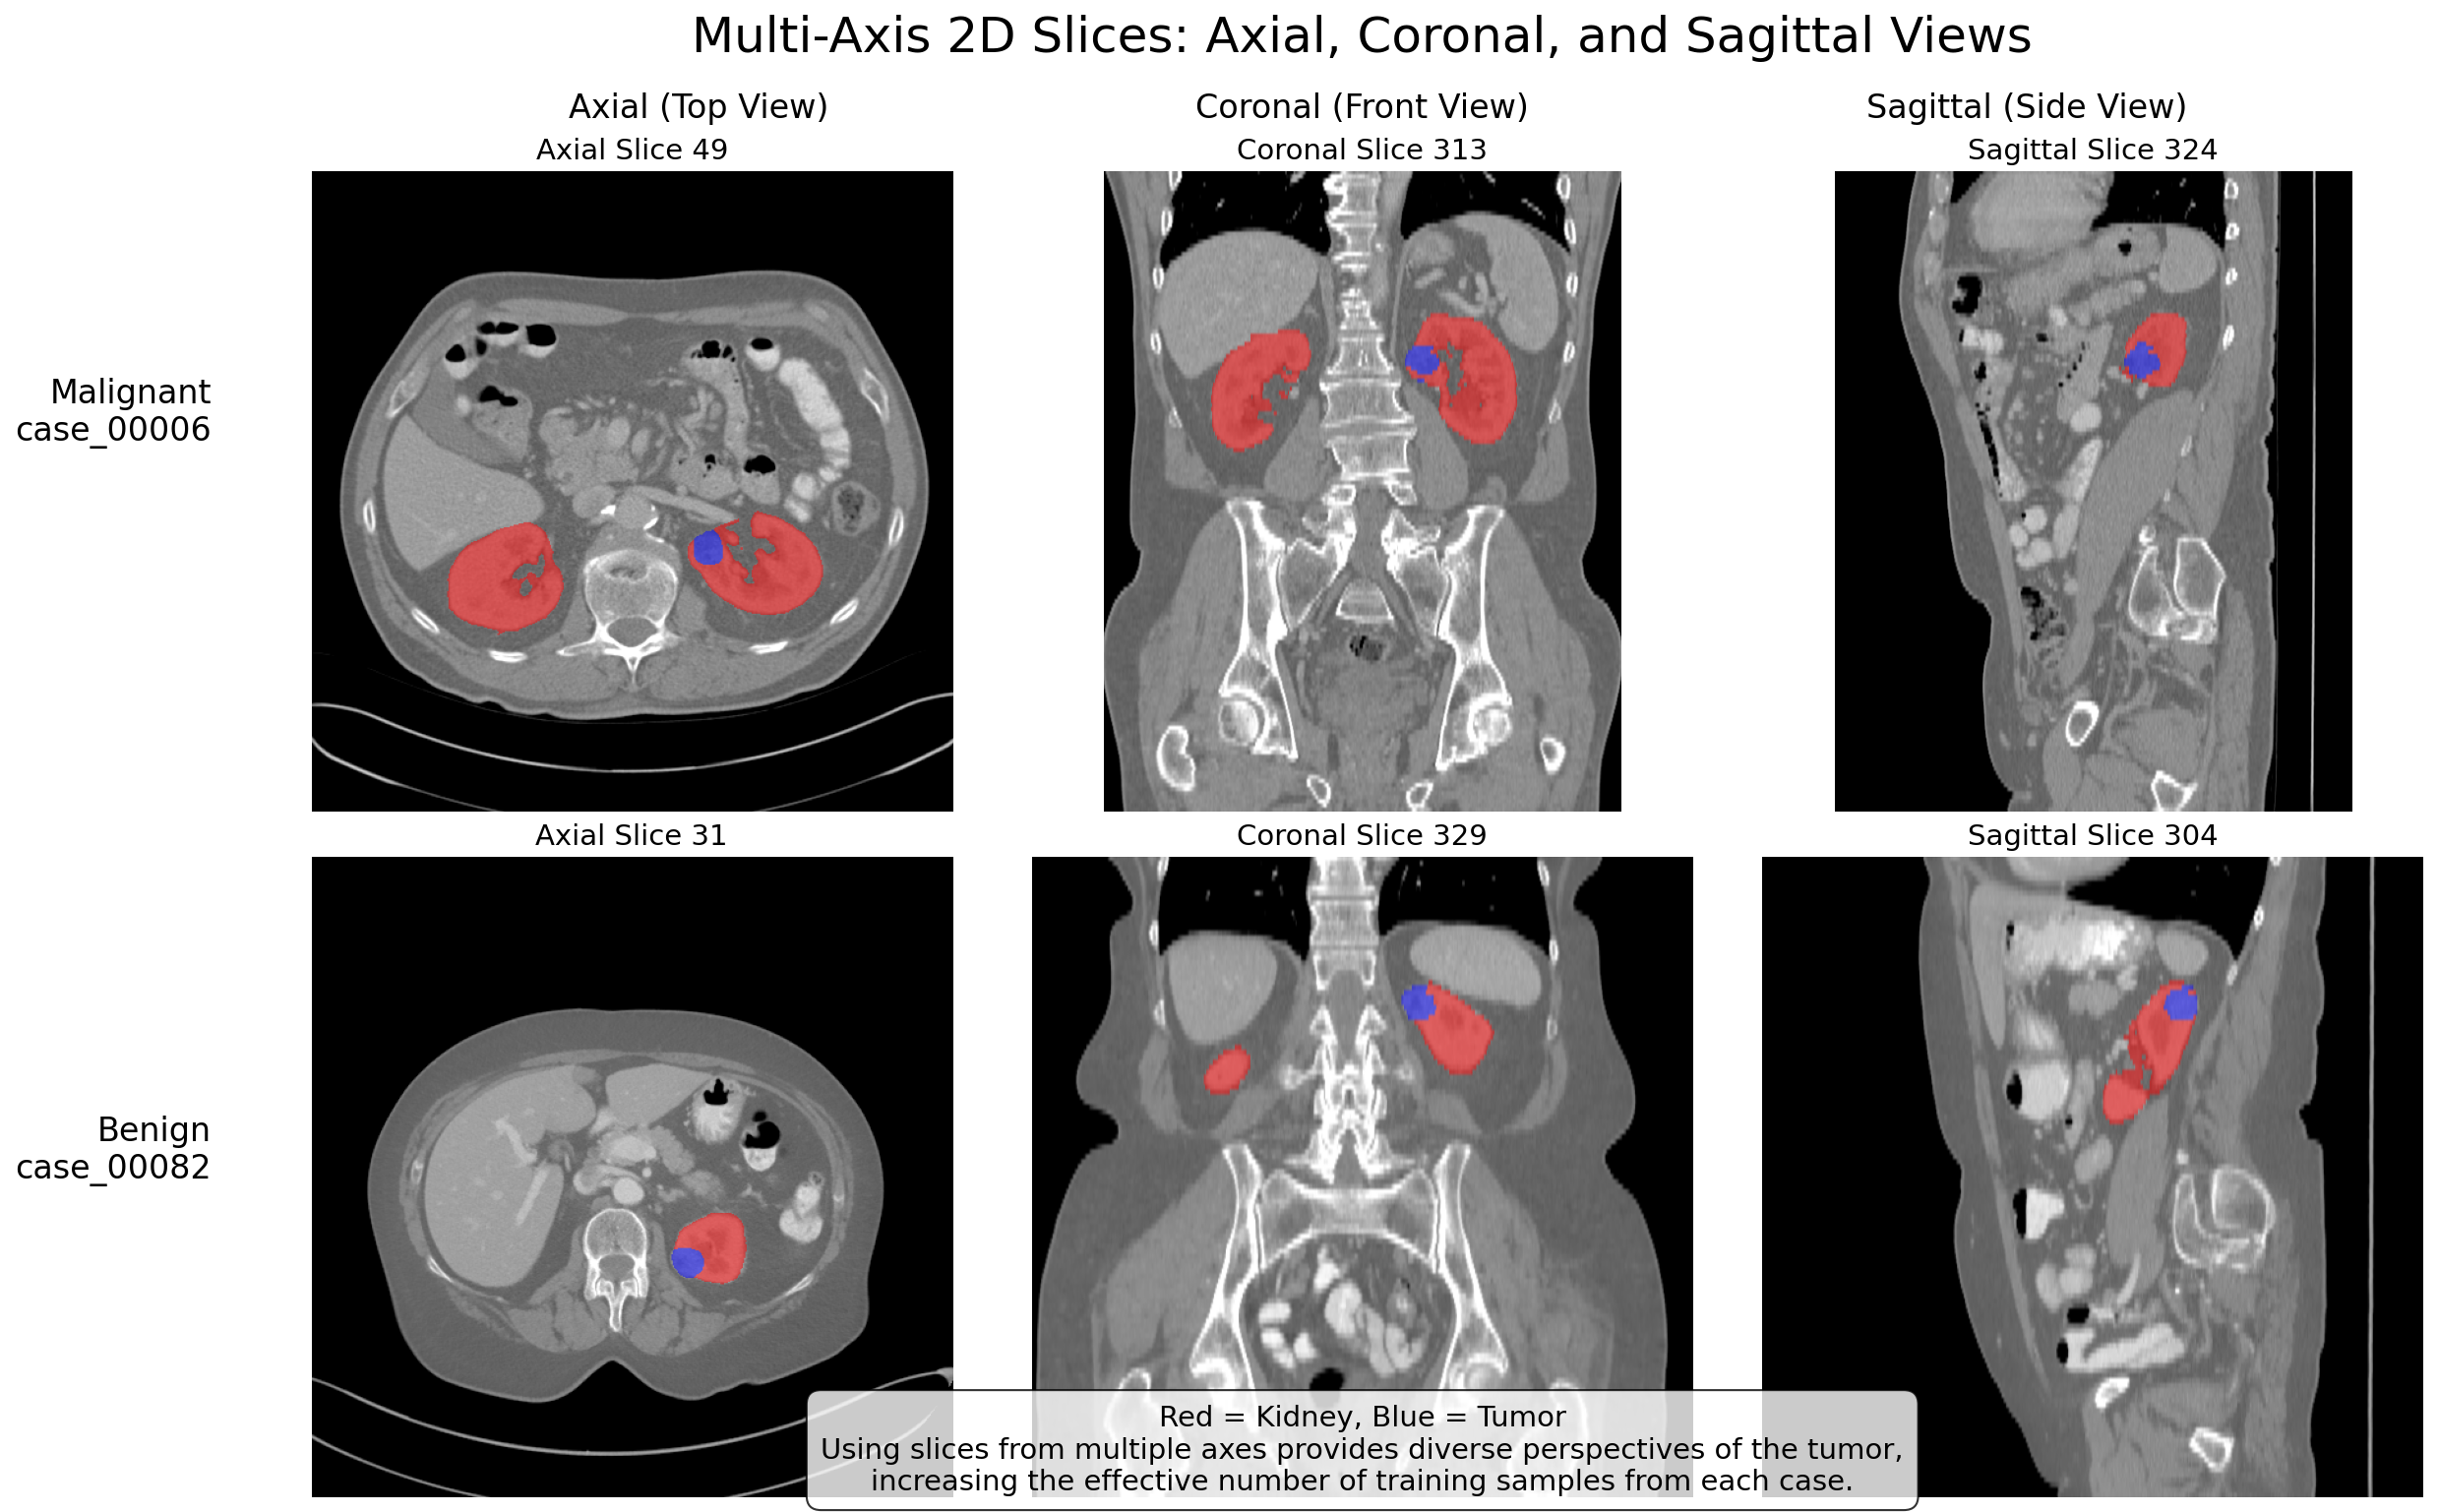

TendersLab developed a state-of-the-art End-to-End (E2E) Deep Learning system serving as a high-fidelity Clinical Decision Support System (CDSS). The model rapidly identifies and classifies kidney tumors as benign or malignant with exceptional accuracy, empowering diagnosing physicians with data-driven insights.

Methodology & Validation

Built as a robust proof-of-concept utilizing a public dataset of 600 CT scans. The E2E architecture bypasses manual segmentation entirely, vastly reducing processing time and human error.